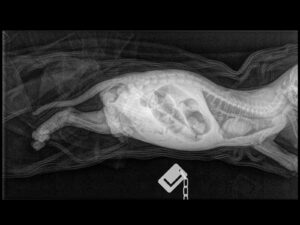

X-Rays